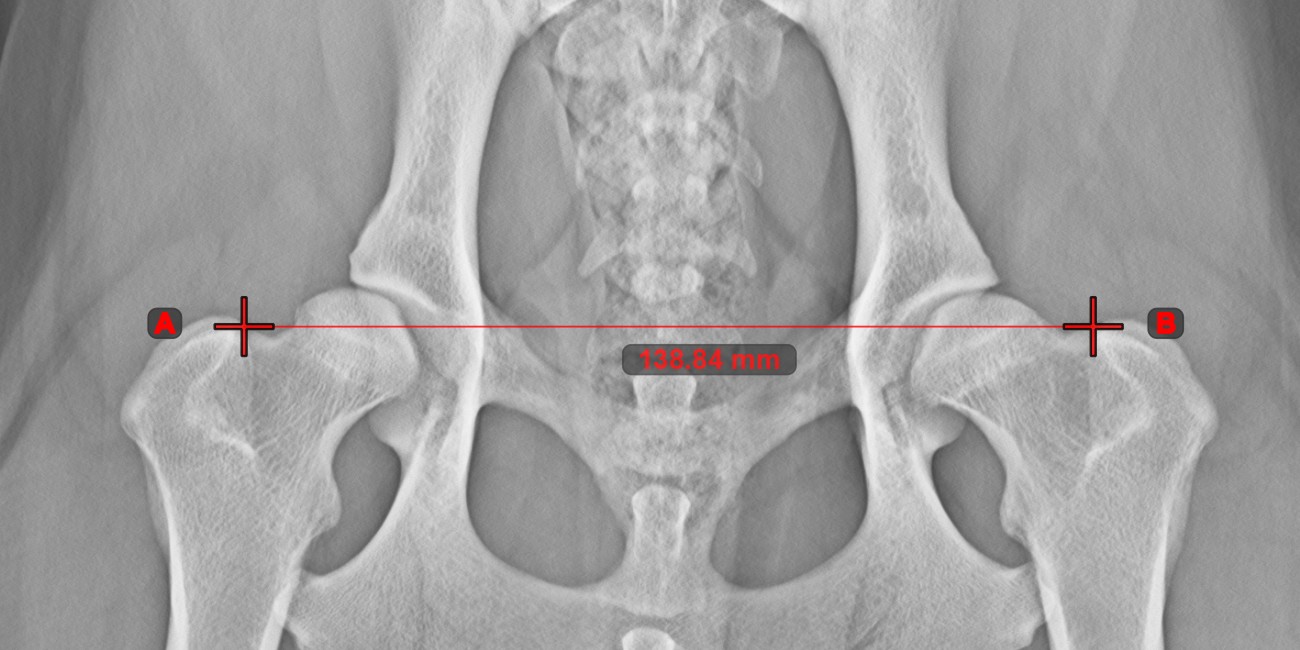

Line Measurement¶

Select the Line Measurement tool and assign it to one of the available mouse buttons. Place the start and end points on the scene or select them from already existing points on the image. The distance between the two points will be automatically

calculated by using the default calibration data, or the recalibrated data by the length calibration measurement.

Modify the start and end point by using the Select/Move Item tool. The distance between the two points will be automatically recalculated.